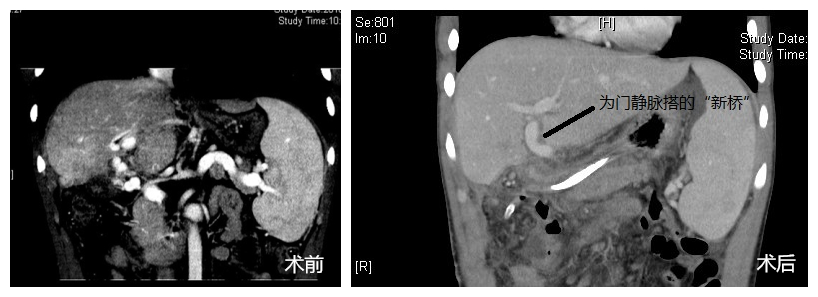

在这场长达10余个小时的手术中,最艰难的地方莫过于寻找到适合搭桥的近端和远端门静脉。而小霆的右肝因外伤后萎缩,左肝代偿性增大和肝门转位,使得原本位于肝脏浅层,通常用于搭桥的门静脉矢状部被深深地包裹在肝内,无法利用。面对这种困难的局面,凭借丰富的临床经验和肝脏手术技巧,耗时4个多小时,董家鸿沿着肝圆韧带向肝内仔细分离,在劈开部分肝脏后终于成功找到左肝门静脉的囊部,通过捐赠的静脉血管,将其与胰腺上方的门静脉连接,完成搭桥。术后超声和CT显示,“桥血管”成功运转,血液流速稳定,源源不断地为小霆的肝脏输送着生命必需的血液和养分。